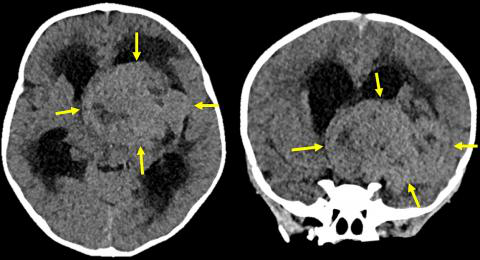

一周:轴位和冠状位非对比头部CT图像显示一个大的边界清楚的等密度(相对于灰质)中线鞍上肿块,中央低密度,可能坏死,病灶。肿块导致梗阻性脑积水,导致中度侧脑室扩大和室周水肿。